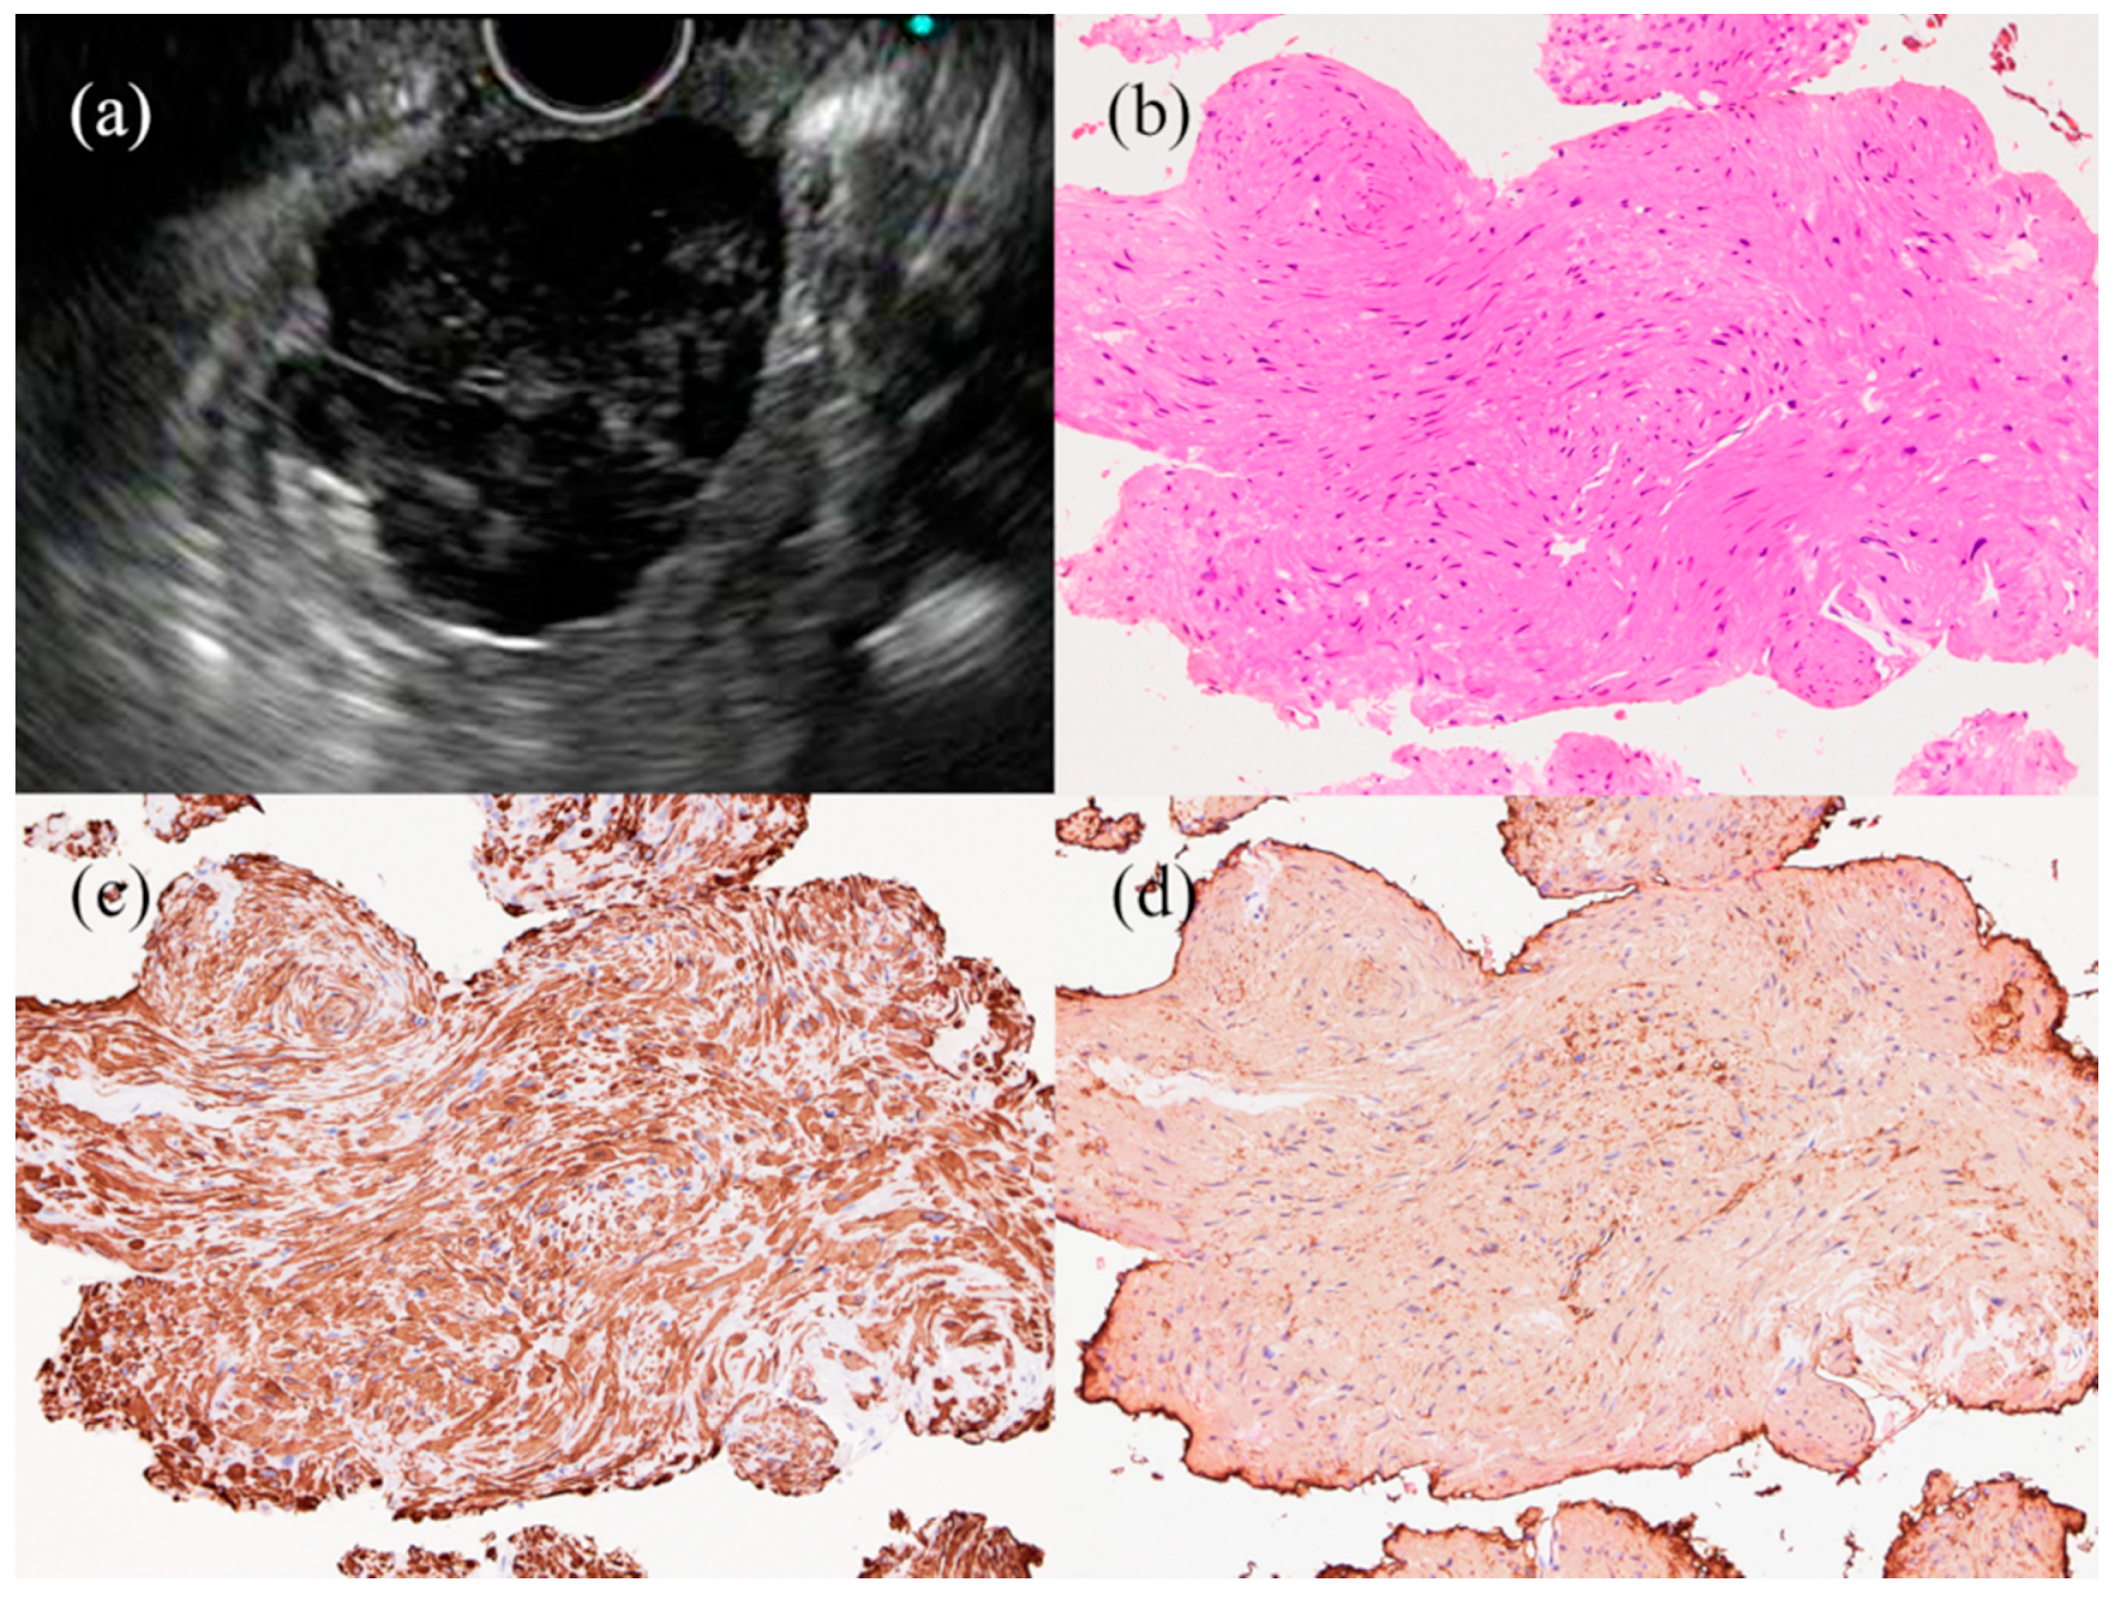

- Fujita, A.; Ryozawa, S.; Kobayashi, M.; Araki, R.; Nagata, K.; Minami, K.; Tanisaka, Y.; Kobatake, T.; Mizuide, M. Diagnostic ability of a 22G Franseen needle in endoscopic ultrasound-guided fine needle aspiration of subepithelial lesions. Mol. Clin. Oncol. 2018, 9, 527–531. [Google Scholar] [CrossRef]

| GIST | 4th | Benign features: small (≤2 cm), oval or round, hypoechoic but relatively hyperechoic compared to muscle layer, homogeneous Malignant features: large (>3 cm), irregular margins, heterogeneous echotexture, cystic spaces, hypervascularity, marginal halo, hyperechoic spots/echogenic foci | KIT (+), CD34 (+), desmin (+), S-100 (-), DOG1 (+), or a mutation search of the KIT or PDGFRA gene | 10–30% clinically malignant |